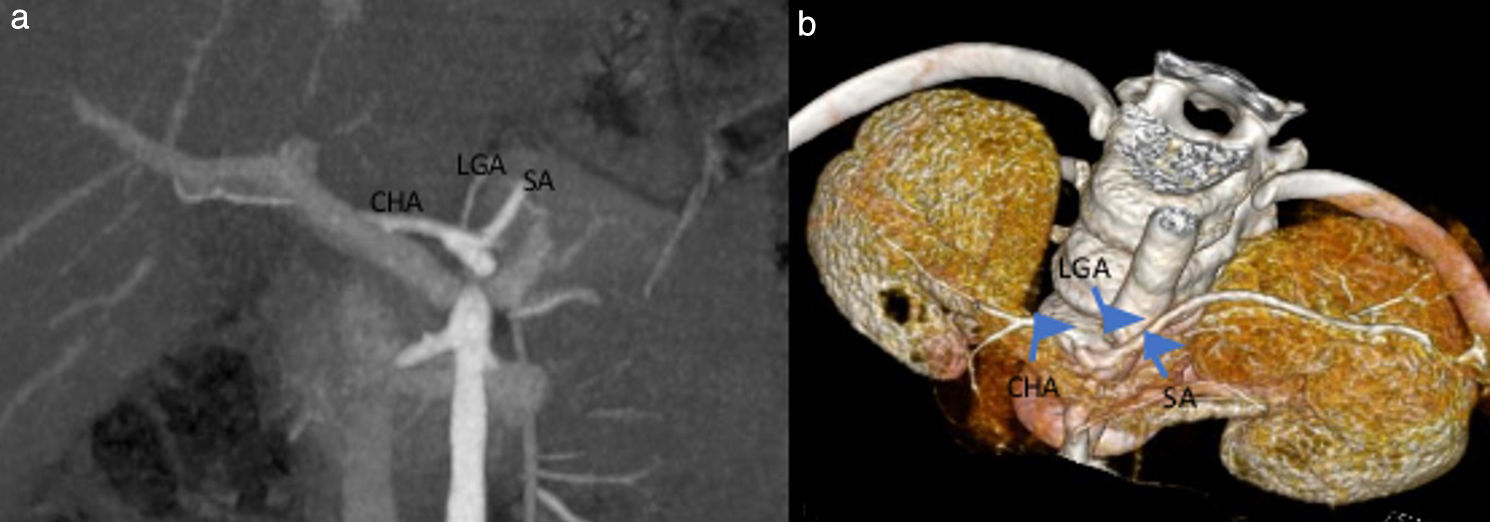

Based on the the Uflacker classification, 159 patients (89.3%) had normal coeliac trunk anatomy (type I) (Fig. 1), 10 cases (5.6%) had gastrosplenic trunk (type V) (Fig. 2), 4 cases (2.2%) coeliac-mesenteric trunk (type VI), 3 (1.7%) absence of the coeliac trunk (type VIII), and 2 cases (1.1%) hepatosplenic trunk (type II) (Table 2).

Gastrosplenic trunk visualized in 3D VR (a) and axial plane MIP images (b), with the common hepatic artery originating from the superior mesenteric artery. CHA, Common hepatic artery; GDA, gastroduodenal artery; LGA, left gastric artery; SA, splenic artery; SMA, superior mesenteric artery.

According to the Michels classification, 80.9% of the patients had normal (type 1) hepatic artery anatomy. The most prevalent variation (4.5%) was an accessory left hepatic artery (type 5) originating from the left gastric artery (LGA) (Fig. 3). In addition, the anatomy in 9 patients could not be defined using the Michels classification. In 5 cases, the variation consisted of the main hepatic artery originating from the abdominal aorta, in 2 of the right hepatic artery originating from the abdominal aorta, in 1 of the right hepatic artery originating from the coeliac trunk, and in 1 of the connection of the main hepatic artery originating from the abdominal aorta and the right hepatic artery originating from the superior mesenteric artery (SMA) (Fig. 4).

Female patient aged 15 years with scimitar syndrome.

3D VR (a) and MIP (b) images show the accessory left hepatic artery branching from the left gastric artery. aLHA, accessory left hepatic artery; CHA, Common hepatic artery; GDA, gastroduodenal artery; LHA, left hepatic artery; LGA, left gastric artery; SA, splenic artery; SMA, superior mesenteric artery.